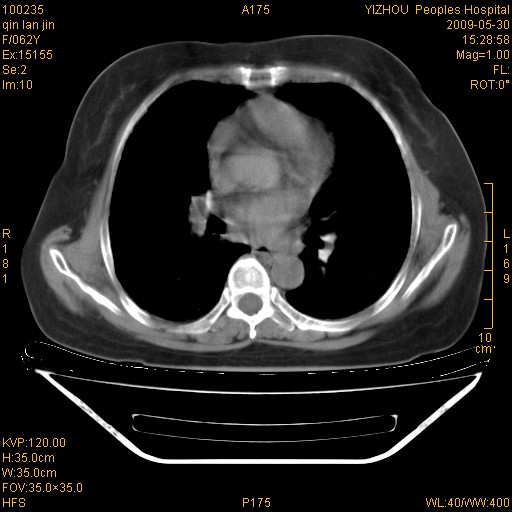

标题: CT20268:肺泡癌?间质性肺炎?

女,62岁,近二年经常咳嗽,近二个月,消瘦、乏力。

纵隔淋巴结大,须排外癌性淋巴管炎

弥漫性双肺间质纤维化。

两肺弥漫性间质性病变(间质性肺炎伴肺间质纤维化?)。